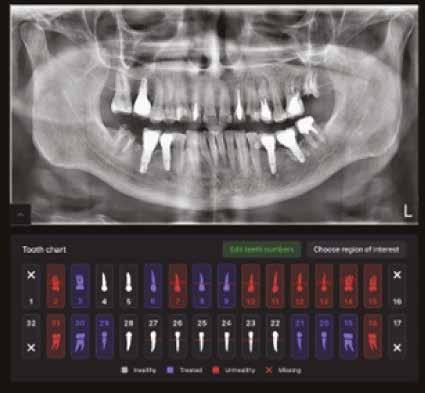

Új dimenzió a CBCT, a fogászati röntgenek és a kefalometriai felvételek diagnosztikájában a MESTERSÉGES

INTELLIGENCIA erejével csak a VIP DENTALBAN!

Dentális státusz elemzése mesterséges intelligencia által CBCT felvételen.

Panorámaröntgen elemzése mesterséges intelligencia által.

Kefalometriai elemzés és pontbejelölés mesterséges intelligencia által.

Legyen az Ön rendelője a fogászati ellátás innovatív központja, és velünk együtt biztosítsa a legmagasabb szintű diagnosztikai szolgáltatást az MI által támogatott elemzésünkkel.